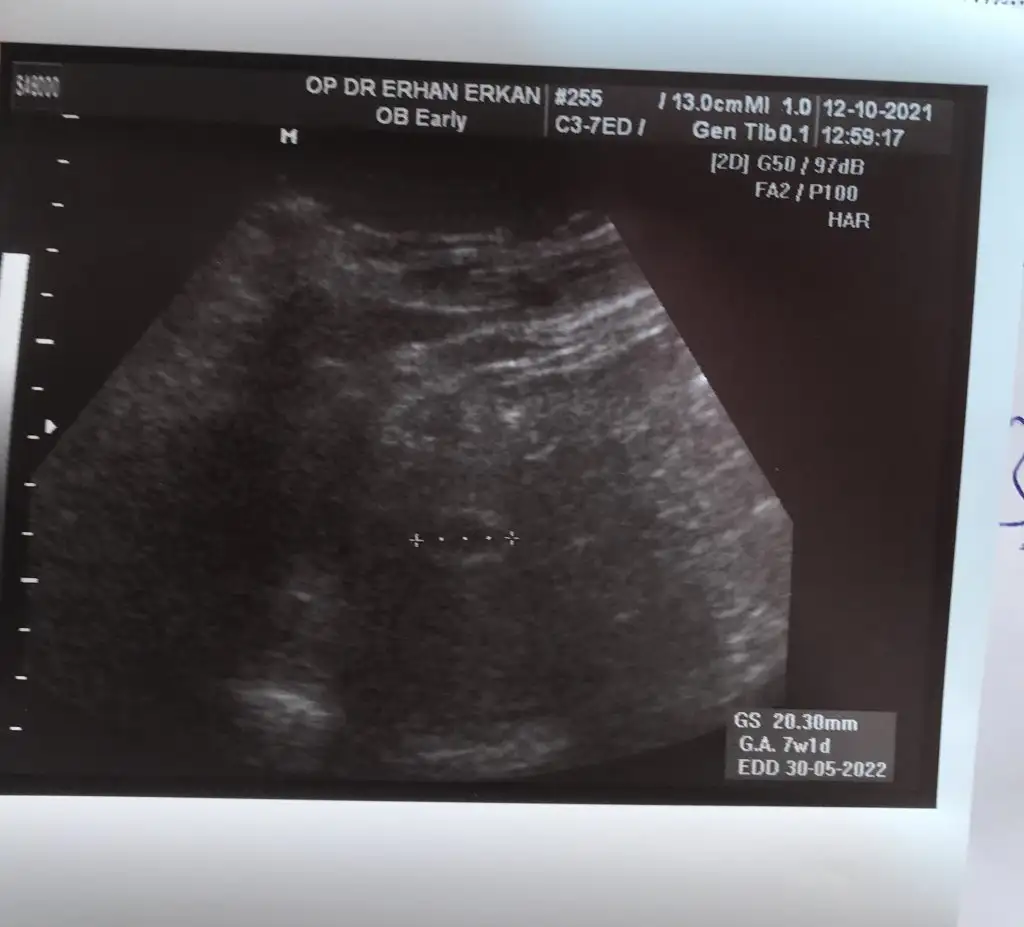

Canim benim 7. Haftamda var ilk ultrasonum yolluyorum sana5+6 yani 6.haftamdaki usg’de belli oldu teori, senin de varsa 6-7.haftaya kadar bakalım beraber tutacak mı

Canim benim 7. Haftamda var ilk ultrasonum yolluyorum sana

Bu arada bu karın ultrasonum5+6 yani 6.haftamdaki usg’de belli oldu teori, senin de varsa 6-7.haftaya kadar bakalım beraber tutacak mı

Sanki sola daha yakın gibi canım, erkek gibi yani ne dersinCanim benim 7. Haftamda var ilk ultrasonum yolluyorum sana

Canim kesenin içinde nereye yakin oldugu onemli degil mi bu teoride ? Burada solda duruyor bence deSanki sola daha yakın gibi canım, erkek gibi yani ne dersin

Evet canım, kesede sola daha yakın geldi bana da, ve karındansa erkek demekmiş ya..Canim kesenin içinde nereye yakin oldugu onemli degil mi bu teoride ? Burada solda duruyor bence de